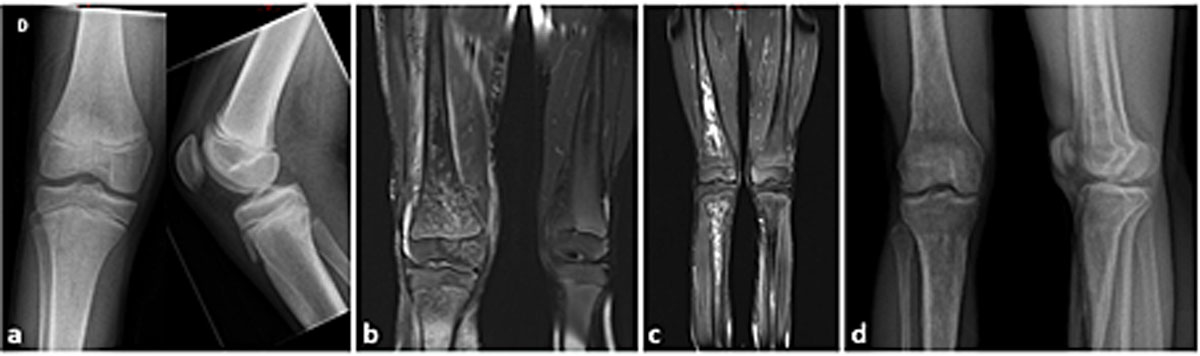

Figure 1 Clinical course of patient 6.

Note the rapid evolution from a normal X-ray on day 1 (a) to persisting defects after 5 years (d), and between magnetic resonance imaging on day 3 (b) and at 10 months (c).